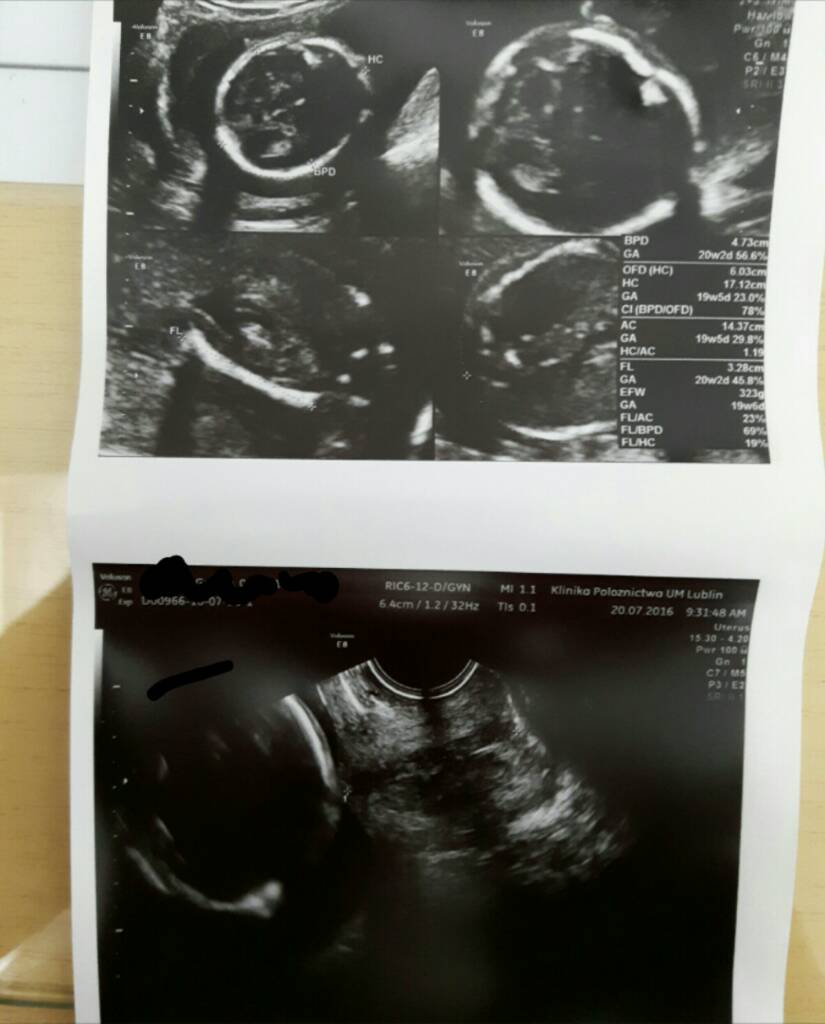

super wiadomosci !ja po wizycie. maluch rosnie jak na drożdżach ma teraz 454g. lekarz mowi ze jego udo poza górną granica i brzuszek tez i mam sie przygotowac na nadejscie ....smoka; )

maluszek bezwiata szans na fikanie bo jest wcisniety do macicy lezy główka w dol obrocony do swiata i nozkami moze pofikac